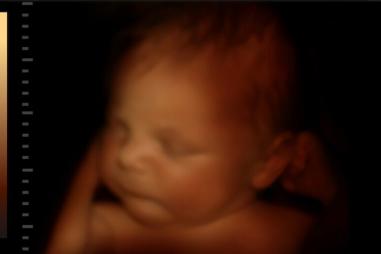

Unborn-baby-late-term-e1713177014919-810x500.jpeg

Kultúra smrti

Poľská žena sa snaží ospravedlniť potrat v 37. týždni kvôli postihnutiu dieťaťa

26.04.2025 POL

V Poľsku prebieha vyšetrovanie po tom, čo lekár vykonal umelý potrat - priame a úmyselné zabitie nenarodeného dieťaťa - v…